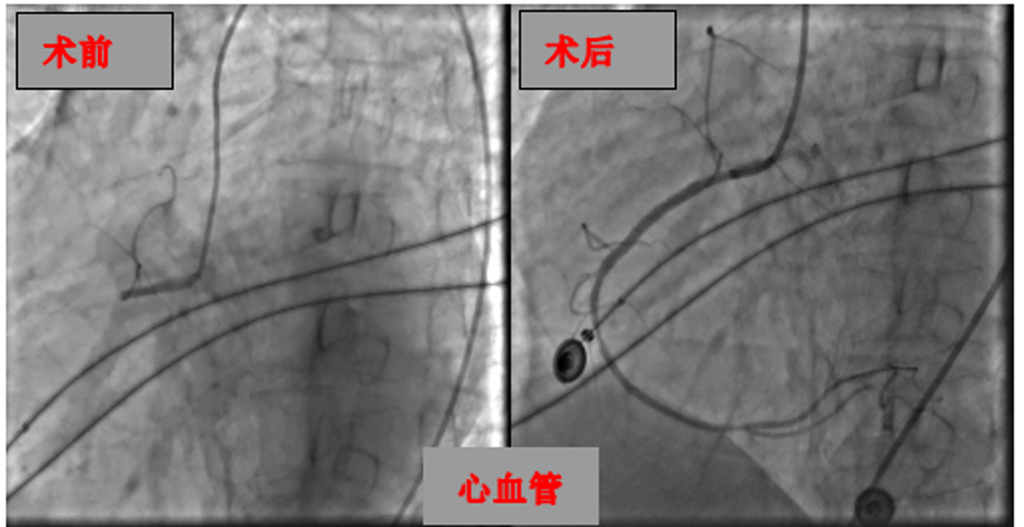

此前,张大爷突发左侧肢体无力、言语不清的紧急状况,急诊医学科接诊后,凭借临床经验高度怀疑脑卒中,第一时间启动卒中绿色通道,同步完成各项化验与头颈部血管检查,快速确诊其右侧颈内动脉、大脑中动脉闭塞,随即紧急转至神经内科进一步救治。在与家属沟通后,决定为其开展急诊血管开通手术,不料手术期间,医学检验科传来超敏肌钙蛋白异常的报告,结合心电图检查,确诊张大爷同时合并冠状动脉闭塞,危急时刻,科室立刻联动心血管内科介入医生同台紧急会诊。

经过多学科医护人员四小时的紧密协作,成功为张大爷开通脑部与心脏的双闭塞血管。术后,张大爷被转入重症医学科接受6天精细化监护与护理,其病情趋于平稳,顺利转至普通病房,目前已进入康复医学科开展针对性后续治疗,身体恢复状况良好。